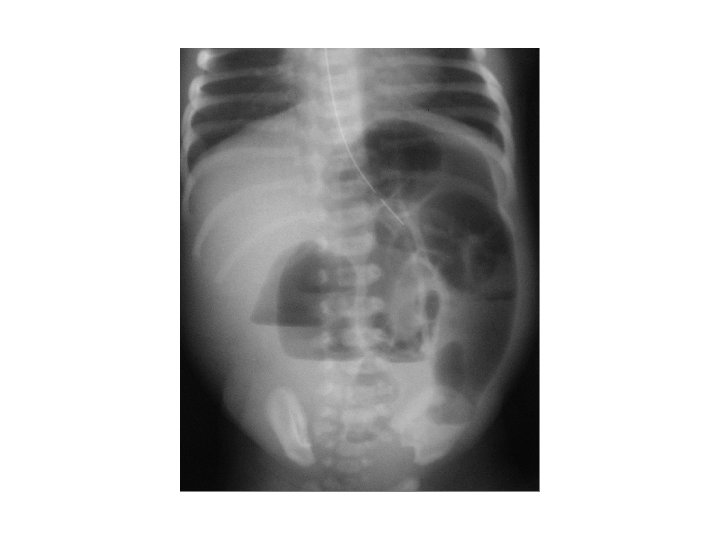

Case 1 Day 12 • On day 12 an Xray was done……

Case 1 Oh, oh…. . • On day 12…. – Free air noted on abdominal XR – No clinical abdominal symptoms • Rx…. – Intubated for transport – NPO – Antibiotic coverage expanded – Transported to Oakland Anna Bergquist CHO MR 960776